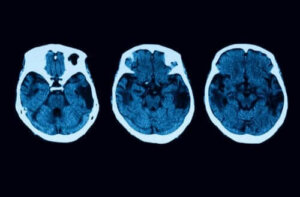

Ancak testler burada bitmiyor; herhangi bir şüpheyi ortadan kaldırmak adına, doktorunuz MRI ve tomografi gibi bazı başka nörolojik testler de yapmak isteyebilir. Eğer posterior kortikal atrofiye dair bir belirti tespit edilirse, bu hastalıkla savaşmanıza yardımcı olacak tedavilerden birine başlamanız gerekecek.